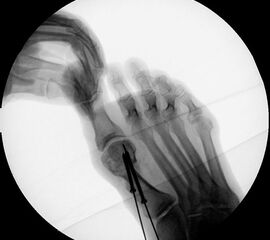

Instrumentarium für die minimalinvasive Vorfußkorrektur.

Abbildung 3

• Fräse für Minimalinvasive Fußchirurgie (Drehzahl: ca. 350 RPM, Drehmoment >50 N/cm).

• Shannon Fräser 20 mm, 2.0 mm Durchmesser.

• Shannon Fräser 12 mm. 2,0

• Bildverstärker.

• Beaver-Blade Messer.

• Mini-Raspatorium.

• Kanülierte Schrauben bis 60 mm Länge.

• Bohrmaschine.

• Kirschnerdrähte mit 1,2 mm (temporäre Fixation) und 2,4 mm (Reposition), special elevator.